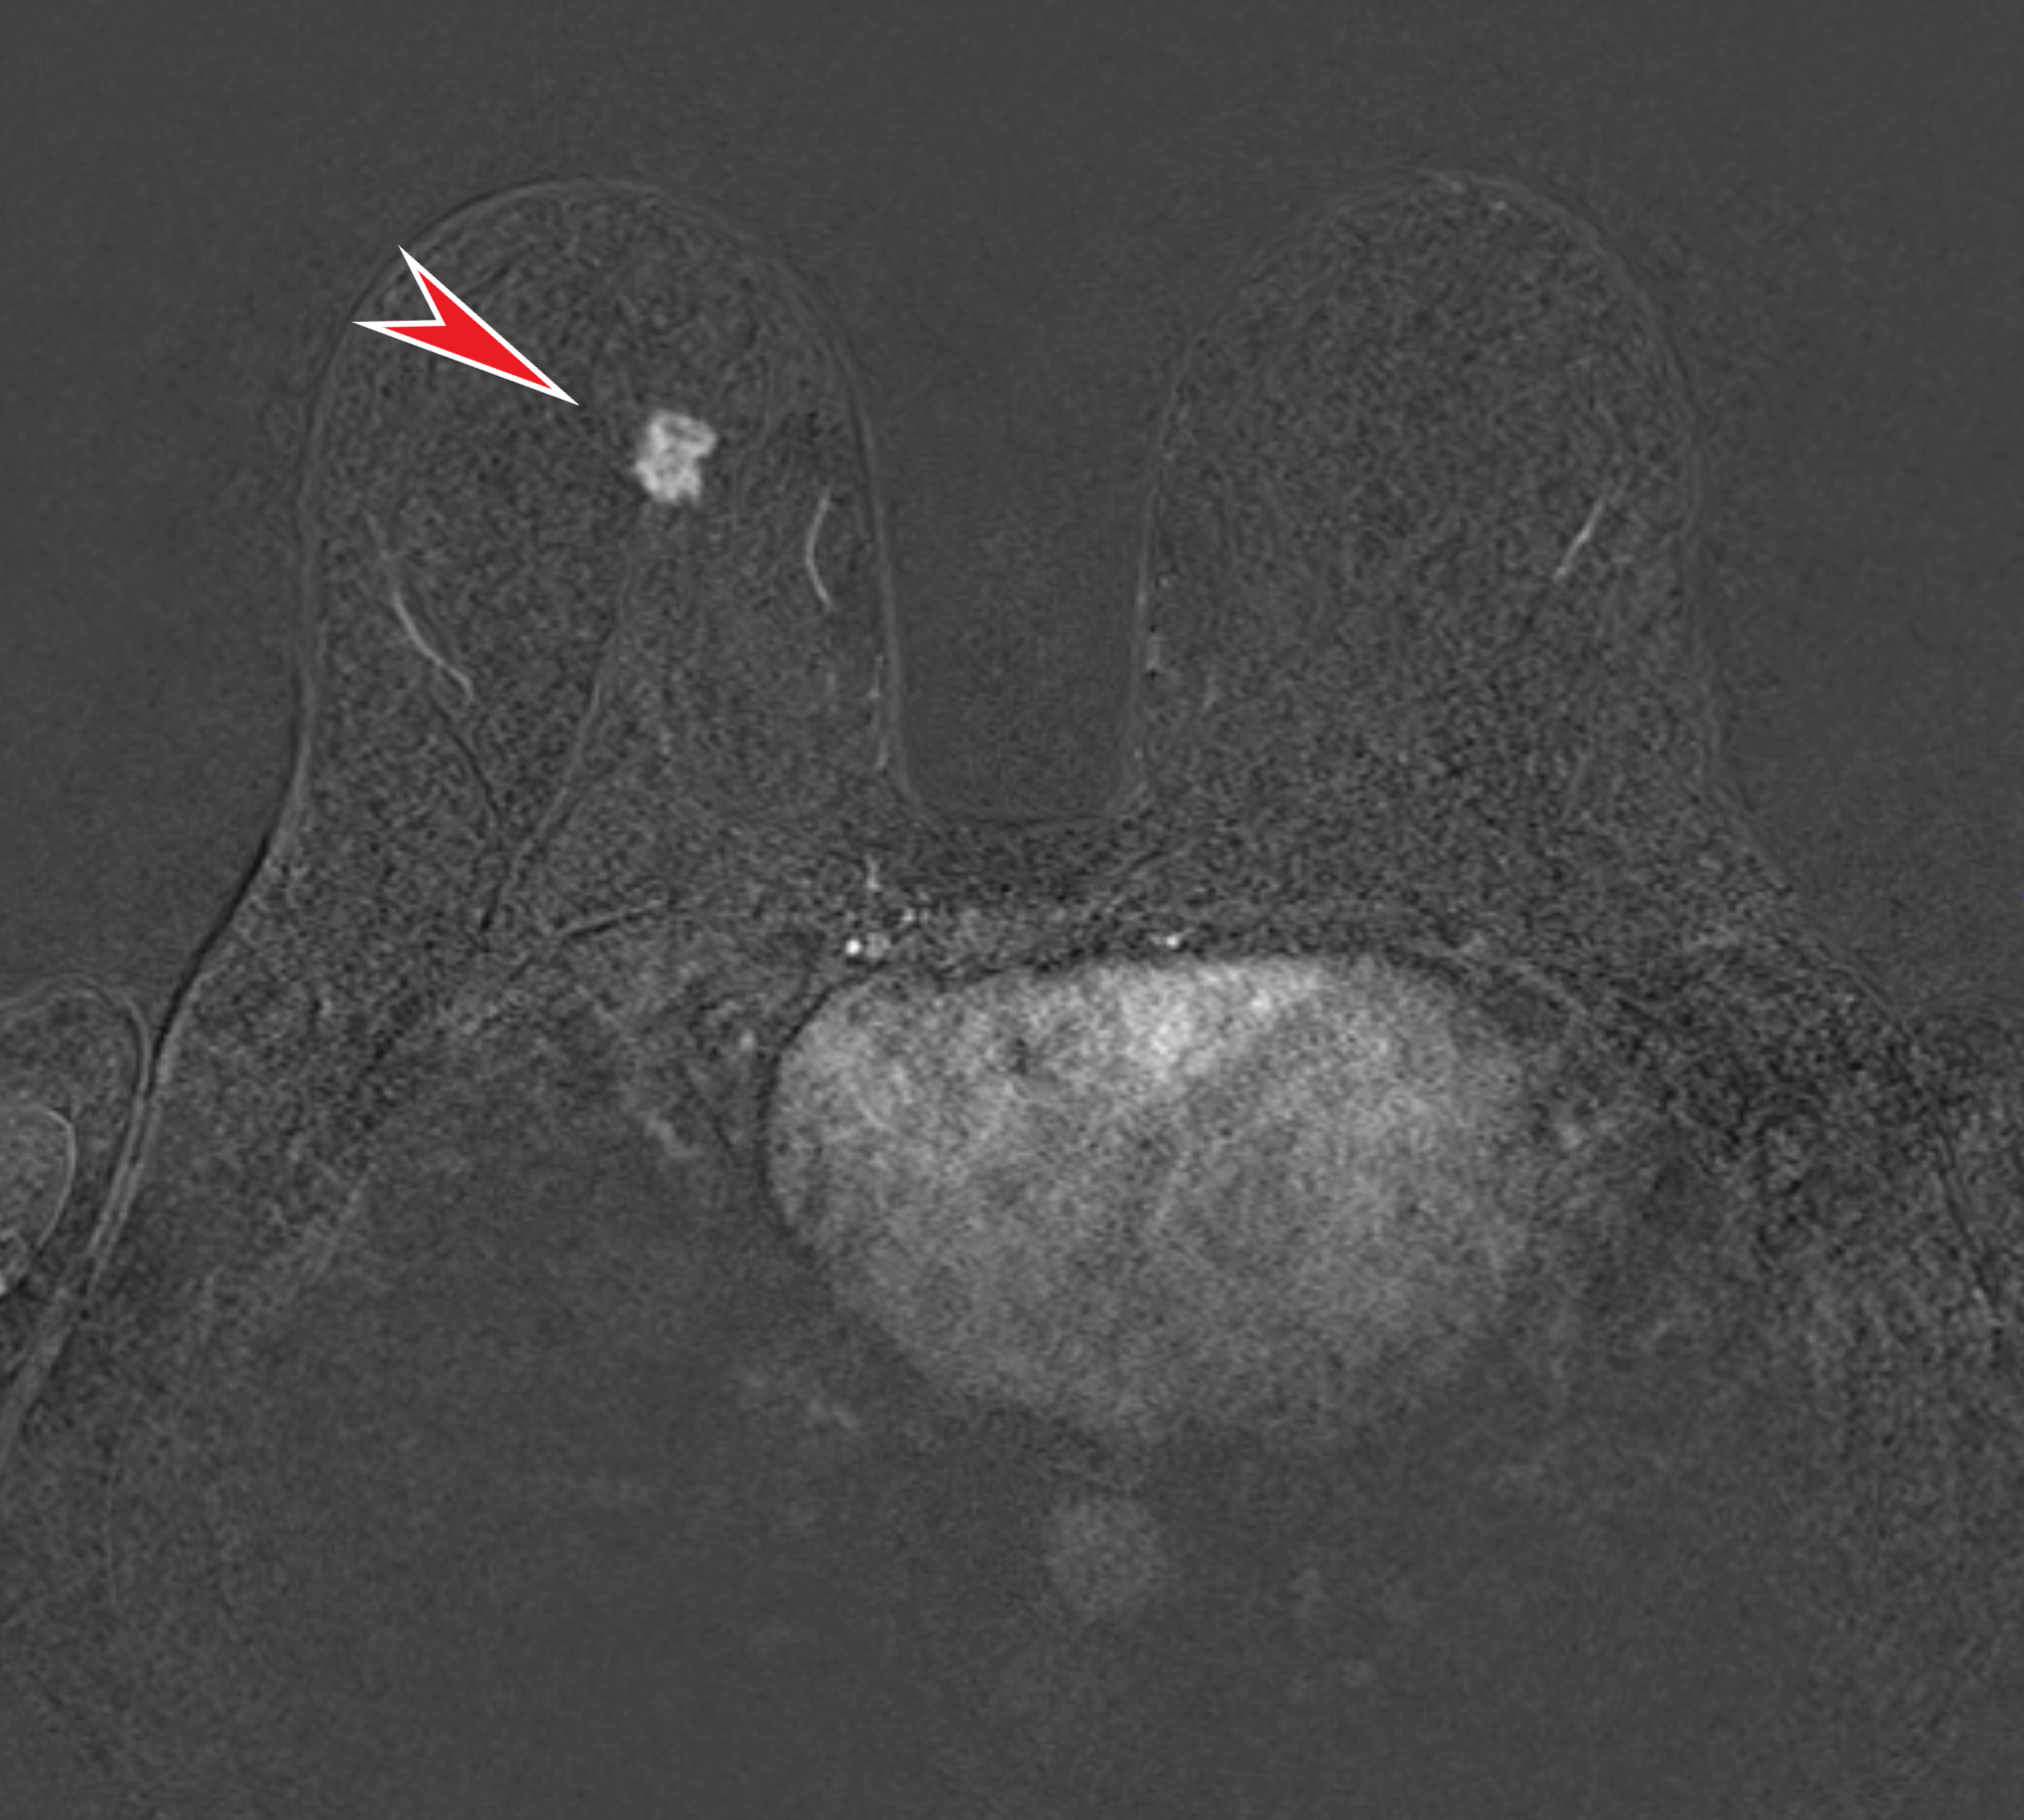

А также относительно гомогенным набором контрастного вещества в раннюю артериальную фазу (т.е. непосредственно сразу после внутривенного введения):

Все вышеуказанные признаки характерны для рака молочной железы, что подтвердила последующая биопсия (проведена тоже мной, под контролем УЗИ):